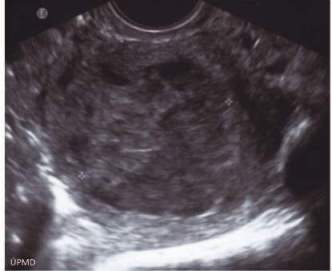

Při vstupním gynekologickém vyšetření před probatorní kyretáží byl shledán normální palpační nález. U pacientky po potvrzení maligního tumoru byla ještě ve spádové nemocnici provedena zbývající stagingová vyšetření. Při ultrazvukovém vyšetřením malé pánve a dutiny břišní byla popsána děloha velikosti 60 x 45 mm, kdy dutina děložní byla rozšířená na 30 mm obsahem smíšené echogenity a s výraznou cévní perfuzí. Viz obr. č. 1.

Obr. č. 1 Ultrazvukový obraz metastázy maligního melanomu choroidei v děložním těle.